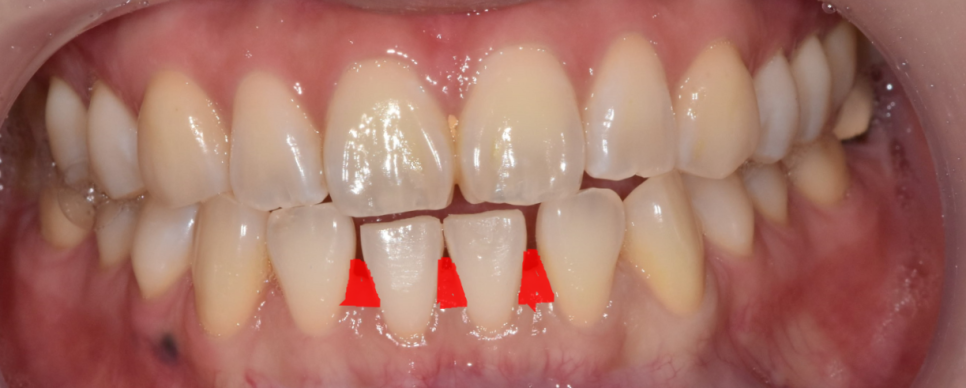

231116

단 2개 앞니 라미네이트 치료를 했을 뿐인데

공간이 메꿔지면서 이미지도 세련되게 변신하셨어요.

벌어진 아래 앞니 공간을 메꾸면 장점 또 한가지

치아 사이로 바람이 안새게 되고

발음 교정 효과까지 있답니다 ㅎㅎ